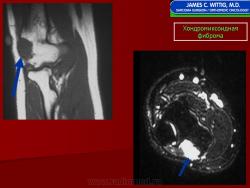

Рентгенологическое исследование показывает, что опухоль растет экзофитно в зоне метафиза и распространяется по направлению к эпифизу. Она имеет четкие и фестончатые очертания. На фоне характерных литических изменений изредка видны участки обызвествления. Наиболее агрессивный вид имеет хондромиксоидная фиброма, локализующаяся в позвонках. Здесь часто отмечается прорастание надкостницы. Макроскопически представляет собой четко отграниченную опухоль, имеющую дольчатое строение, плотную консистенцию, серовато-белый или синюшно-серый цвет. При прорастании новообразования через кортикальный слой надкостница сохраняется. В редких случаях наблюдается имплантация опухолевой ткани в окружающие мягкие ткани. Для лечения хондромиксоидной фибромы используется кюретаж. Рецидивы наблюдаются в 10—15 % случаев, обычно в течение первых 2 лет после операции, чаще всего у лиц моложе 15 лет.

Рентгенологическая картина. Хондромиксоидная фиброма длинных трубчатых костей в типичных случаях представлена метафизарным или метадиафизарным, эксцентричным, четко очерченным, овальным очагом разряжения костной ткани с истон чением и вздутием коркового слоя с одной стороны.

Рентгенологическое исследование показывает, что опухоль растет экзофитно в зоне метафиза и распространяется по направлению к эпифизу. Она имеет четкие и фестончатые очертания. На фоне характерных литических изменений изредка видны участки обызвествления. Наиболее агрессивный вид имеет хондромиксоидная фиброма, локализующаяся в позвонках. Здесь часто отмечается прорастание надкостницы. Макроскопически представляет собой четко отграниченную опухоль, имеющую дольчатое строение, плотную консистенцию, серовато-белый или синюшно-серый цвет. При прорастании новообразования через кортикальный слой надкостница сохраняется. В редких случаях наблюдается имплантация опухолевой ткани в окружающие мягкие ткани. Для лечения хондромиксоидной фибромы используется кюретаж. Рецидивы наблюдаются в 10—15 % случаев, обычно в течение первых 2 лет после операции, чаще всего у лиц моложе 15 лет.